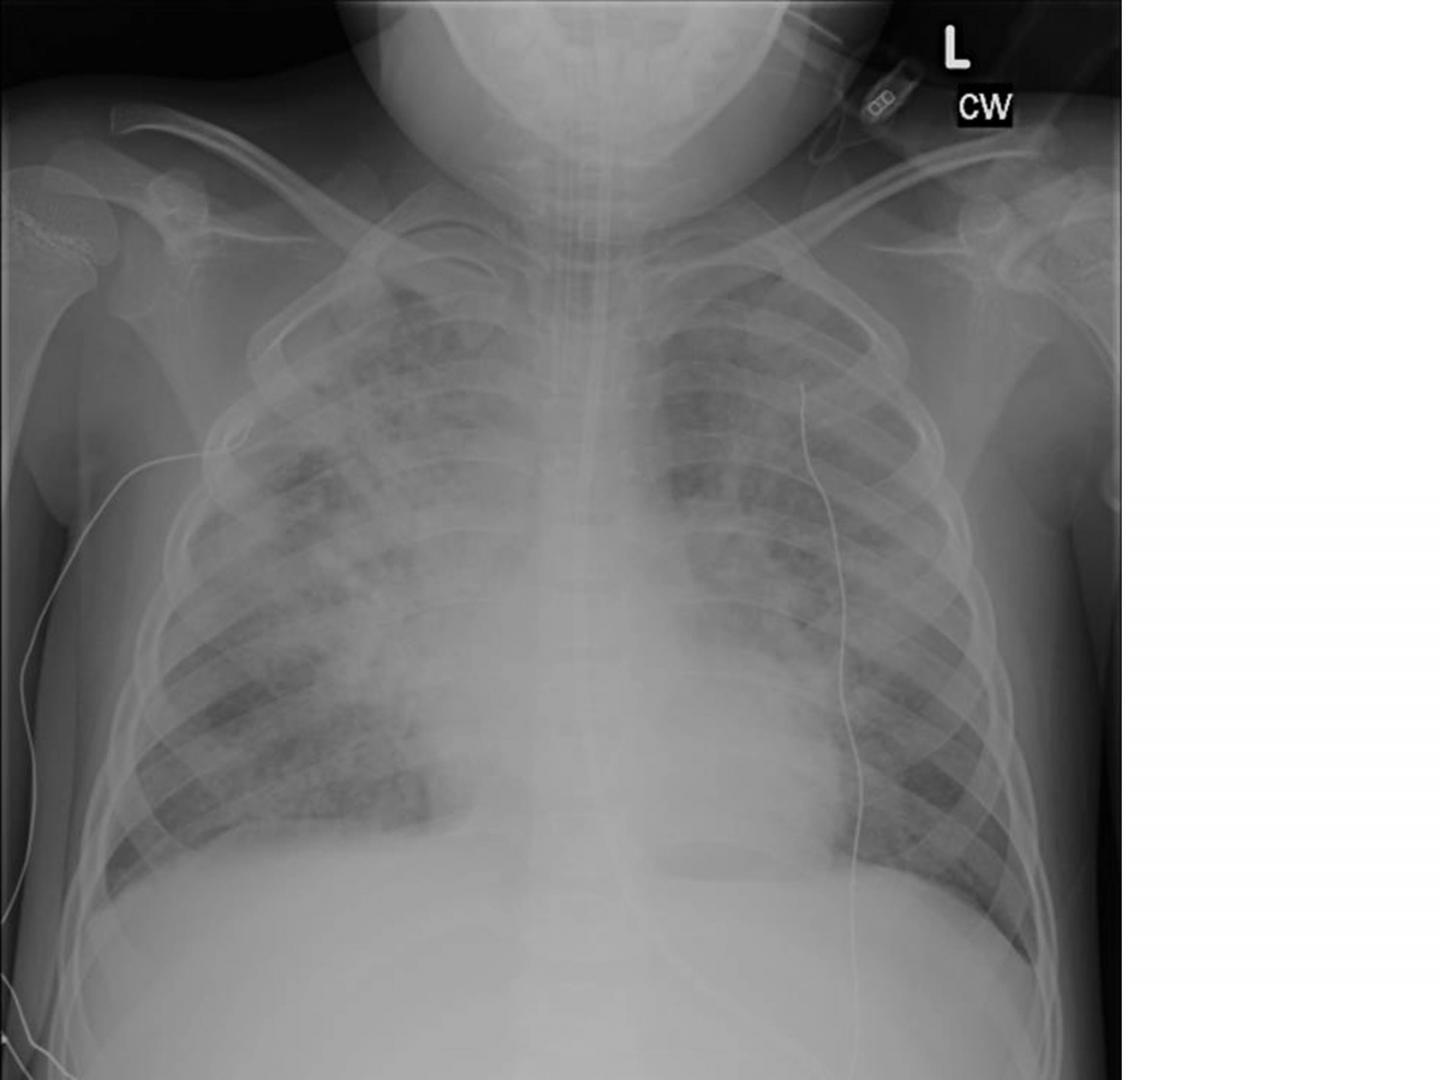

image: This is a chest x-ray of a child with Pediatric Acute Respiratory Distress Syndrome. The cloudy white area in the chest represents areas of lung which have been damaged and cannot function normally. As a result, the child has an endotracheal (breathing) tube which is connected to a mechanical ventilator.

According to a first-of-its-kind international study, a new definition of Pediatric Acute Respiratory Distress Syndrome (PARDS) results in a more accurate diagnosis of many more children with the rapidly progressive disease than the widely used adult definition.

Acute respiratory distress syndrome causes fluid to leak into the lungs, making it very difficult to breathe and leading to low oxygen in the blood, called hypoxemia. Pediatric intensivists have long recognized that the condition manifests differently in children than in adults. However, until recently, there was no pediatric-specific diagnostic criteria.